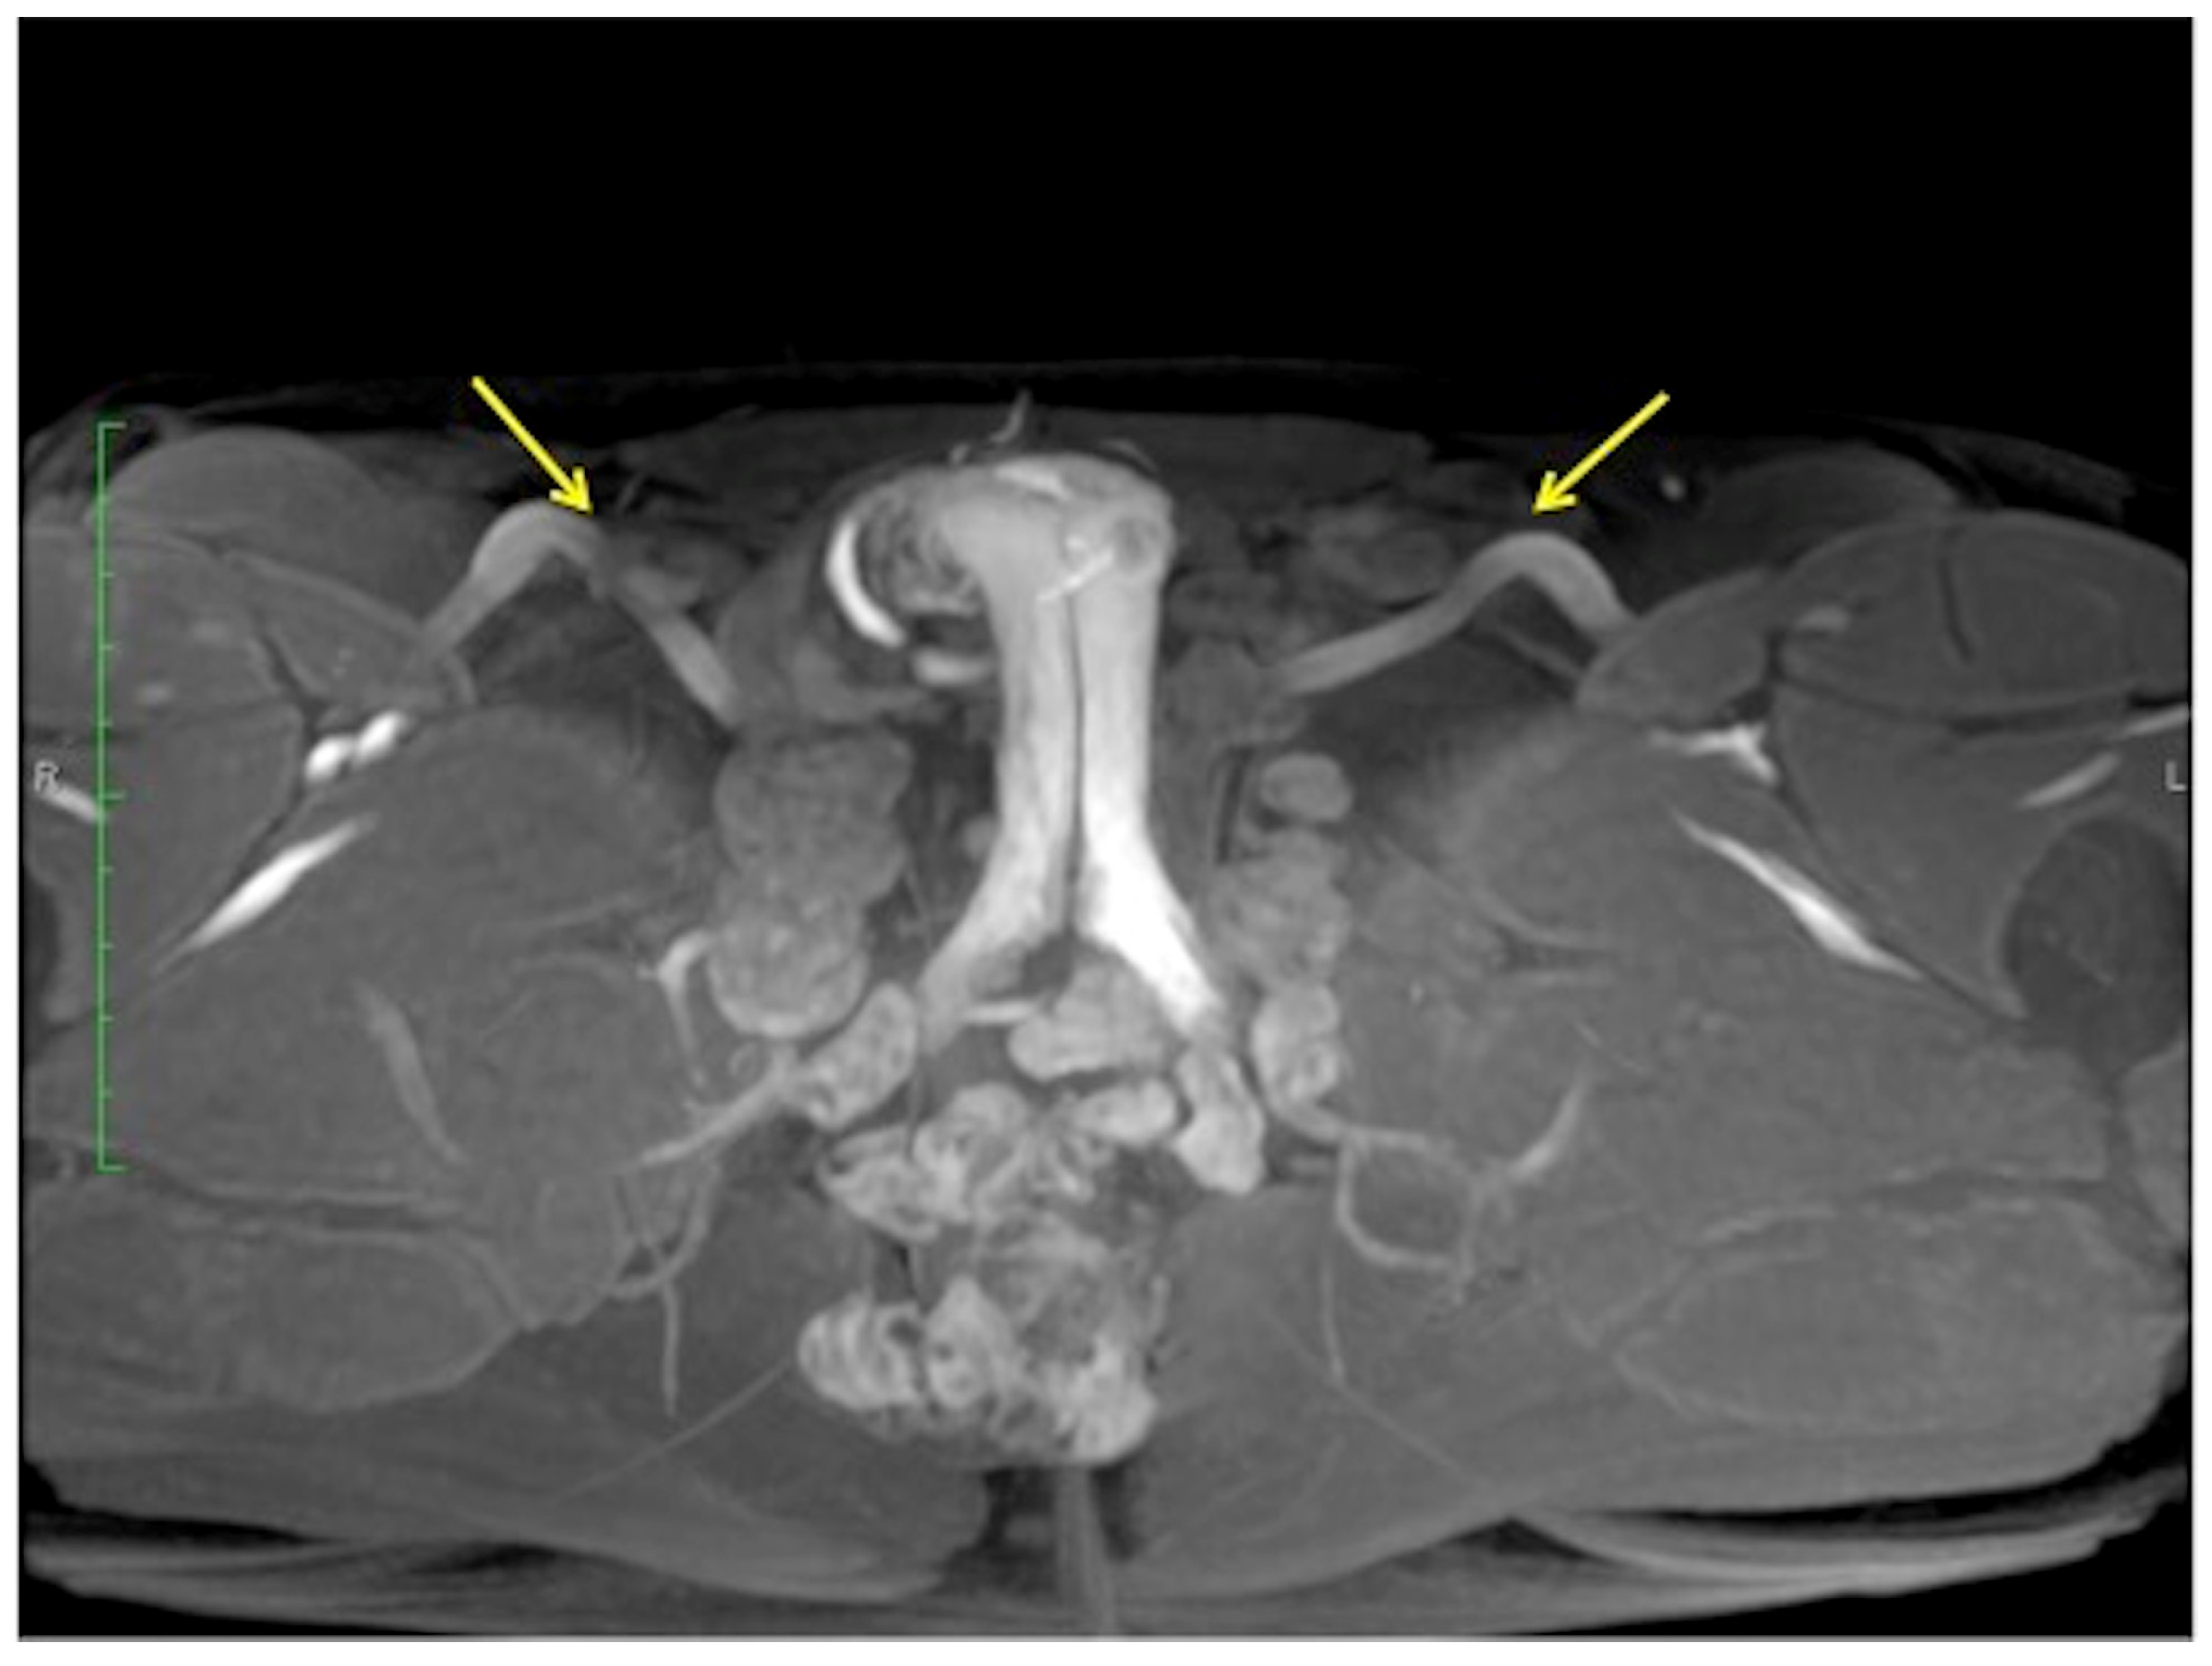

Figure 8.

Cav-MRI. GRE T1W 3D FS axial image displayed with MIP reconstruction shows an ineffective erection supported by superficial venous leakage mediated by the external pudendal veins (arrows).